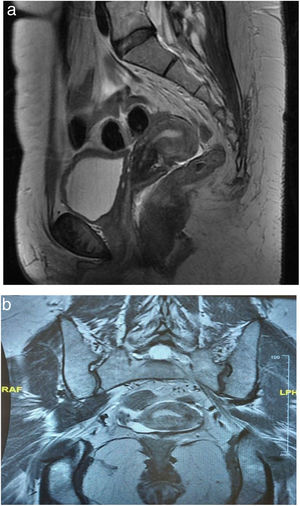

Diagnostic evaluationThe vaginal ultrasound revealed a retroverted uterus of 57mm×27mm×34mm (Fig. 1). Internal contour showed a 7mm indentation compatible with septum. Endometrial thickness was 5mm. Right ovary was nor visualized, nor left one. No free liquid was observed at Douglas space. A pelvic magnetic resonance was requested and absence of the ovaries was confirmed (Fig. 2). At that time, due to the suspicion of an underlying syndromic alteration, a genetic study was requested and reported a 46XY karyotype as well as a heterozygous mutation of variant c 1432+4C>T in intron 9 of the WT1 gene (IVS9+4C>T; NM:024426.4), which was diagnostic of Frasier syndrome.